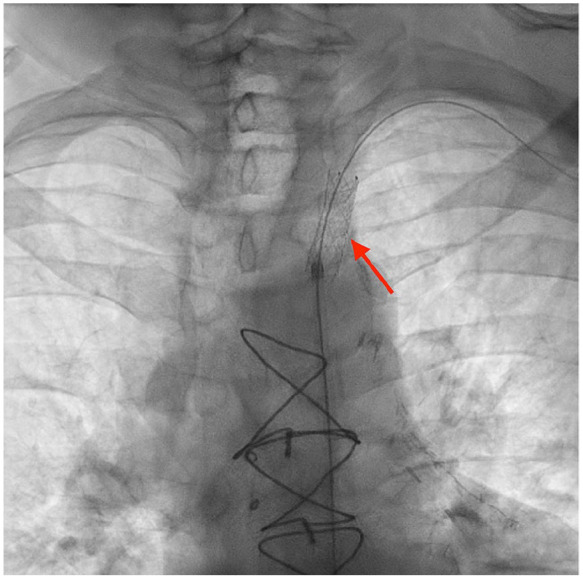

冠状动脉-锁骨下窃血综合征(CSSS)是冠状动脉旁路移植术(CABG)累及左乳内动脉(LIMA)后罕见但重要的并发症,通常是由于近端锁骨下动脉狭窄。我们报告一位54岁男性,既往有三支血管冠脉搭桥(LIMA至左前降),并发急性胸痛和肌钙蛋白水平升高。心电图示弥漫性st段改变。急诊血管造影显示移植物通畅,但左锁骨下动脉近LIMA起始处90%狭窄。病变通过经皮血管成形术和药物洗脱支架置入术成功治疗,症状得以缓解,心功能得以保留。CSSS虽然不常见,但在冠状动脉搭桥后复发性心绞痛或心肌损伤的患者中,尽管移植物未闭,仍应考虑CSSS。文献估计锁骨下狭窄高达5%的CABG候选者,但常规筛查仍然不一致。本病例强调了CSSS是一种可逆的缺血原因,并强调了在选定的患者中进行靶向血管成像的价值。

Coronary-subclavian steal syndrome (CSSS) is a rare but important complication following coronary artery bypass grafting (CABG) involving the left internal mammary artery (LIMA), typically due to proximal subclavian artery stenosis. We present a 54-year-old male with prior triple-vessel CABG (LIMA to left anterior descending) who developed acute chest pain and elevated troponin levels. Electrocardiogram showed diffuse ST-segment changes. Emergent angiography revealed patent grafts but critical 90% stenosis of the left subclavian artery proximal to the LIMA origin. The lesion was successfully treated with percutaneous angioplasty and drug-eluting stent placement, resulting in the resolution of symptoms and preserved cardiac function. CSSS, though uncommon, should be considered in post-CABG patients with recurrent angina or myocardial injury despite patent grafts. Literature estimates subclavian stenosis in up to 5% of CABG candidates, yet routine screening remains inconsistent. This case highlights CSSS as a reversible cause of ischemia and underscores the value of targeted vascular imaging in selected patients.